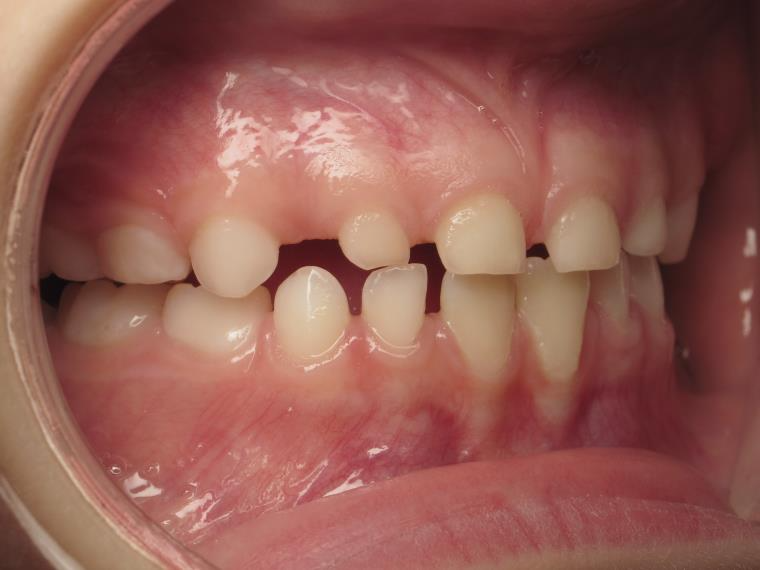

12 béance inversé droit 4 ans

inversion postérieur coté droit et espace entre les dents du haut et du bas (diastèmes)

bilan début et en cours de traitement